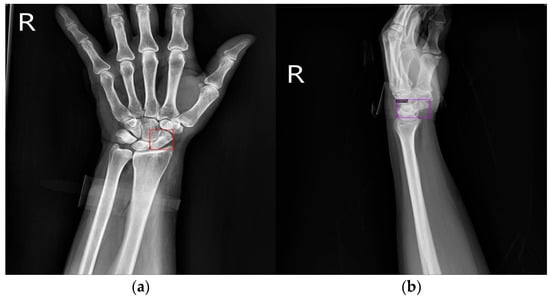

The human wrist consists of eight carpal bones, with the scaphoid bone being the largest. Located under the thumb and near the arm, as indicated by the red box in Figure 1, the scaphoid is prone to injury because of its location. It can fracture not only from severe accidents but also from falls where one braces themselves with the wrist or during athletic activities. A scaphoid fracture may not always cause severe pain; symptoms can be mild, leading individuals to believe they have merely sprained their wrist and that it will heal without medical intervention. Scaphoid fractures account for 2% to 7% of all fractures and 60–70% of carpal bone fractures. General treatment often involves screw fixation surgery because of its short operation time and good recovery outcomes. However, accurate localization of both the scaphoid and the fracture site is essential for implanting the screw at the optimal angle. Physicians typically use X-rays for diagnosis, but since X-rays are two-dimensional projections of a three-dimensional object, the scaphoid bone may overlap and not be fully visible in the two-dimensional image. This is particularly problematic for non-displaced fractures, which can be challenging to detect with the naked eye and are termed occult fractures, as shown in Figure 2.

Figure 1.

The location of the scaphoid bone. The scaphoid bone is within the red box.

Figure 2.

Scaphoid bone fractures under different conditions. (a) Occult fracture; (b) non-displaced fracture (hairline crack); and (c) displaced fracture.